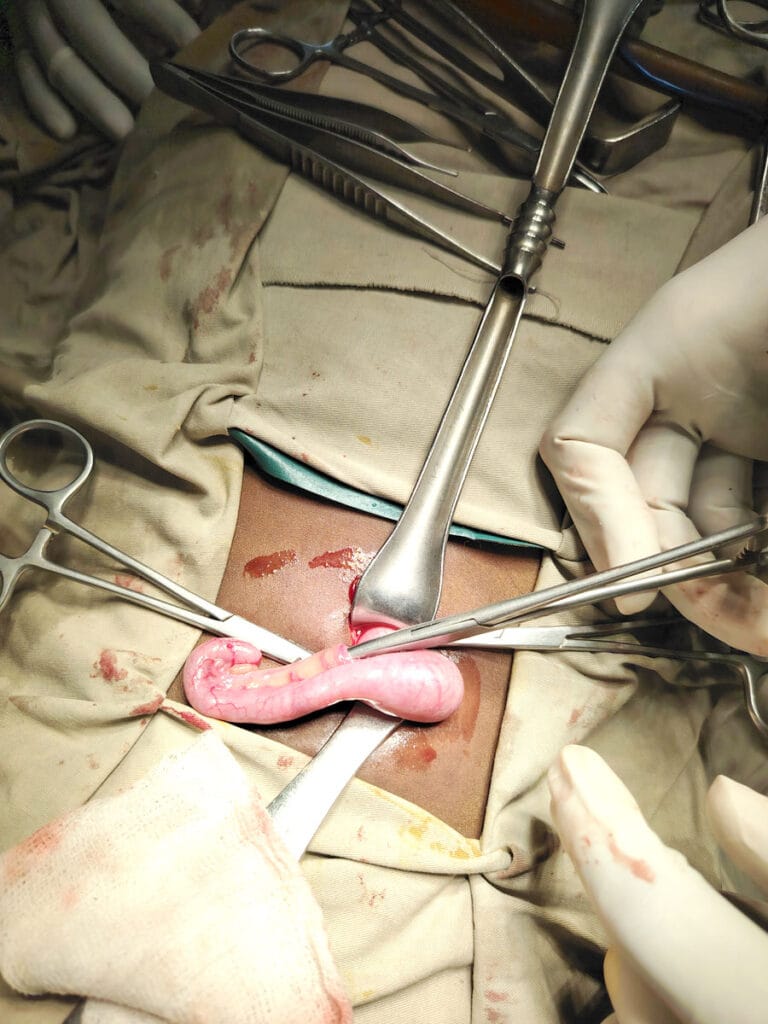

- Intussusception